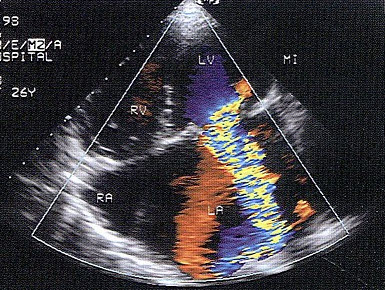

42、单项选择题

该图表明()